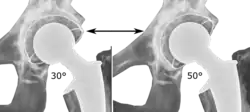

The direction of the acetabular cup influences the range of motion of the leg, and also affects the risk of dislocation.[16] For this purpose, the acetabular inclination and the acetabular anteversion are measurements of cup angulation in the coronal plane and the sagittal plane, respectively.